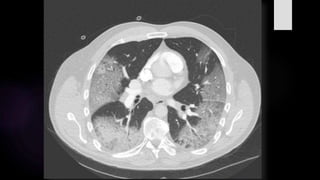

Lóbulo superior derecho: 50% (03 ptos)

Lóbulo medio derecho: 30% (03 ptos)

Lóbulo inferior derecho: 60% (04 ptos)

Lóbulo superior izquierdo: 60% (04 ptos)

Lóbulo inferior izquierdo: 80% (05 ptos)

Puntuación: 19 ptos

CONCLUSIÓN: AFECCIÓN SEVERA

CONCLUSIÓN: AFECCIÓN SEVERA –

CATEGORIA B (PATRÓN EMPEDRADO)